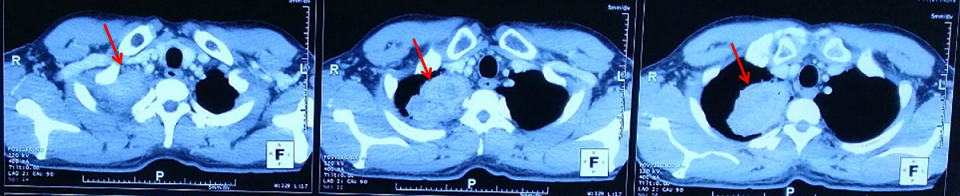

Chụp cắt lớp vi tính lồng ngực sau điều trị: Hình ảnh khối u thùy trên phổi phải kích thước 3×2 cm

So sánh trước và sau điều trị:

Trước điều trị: Hình ảnh khối u thùy trên phổi phải kích thước 5x6cm

Sau điều trị 6 tháng: Hình ảnh khối u thùy trên phổi phải kích thước 3×2 cm

Sau điều trị 9 tháng:

Hình ảnh khối u thùy trên phổi phải kích thước 1×2 cm.